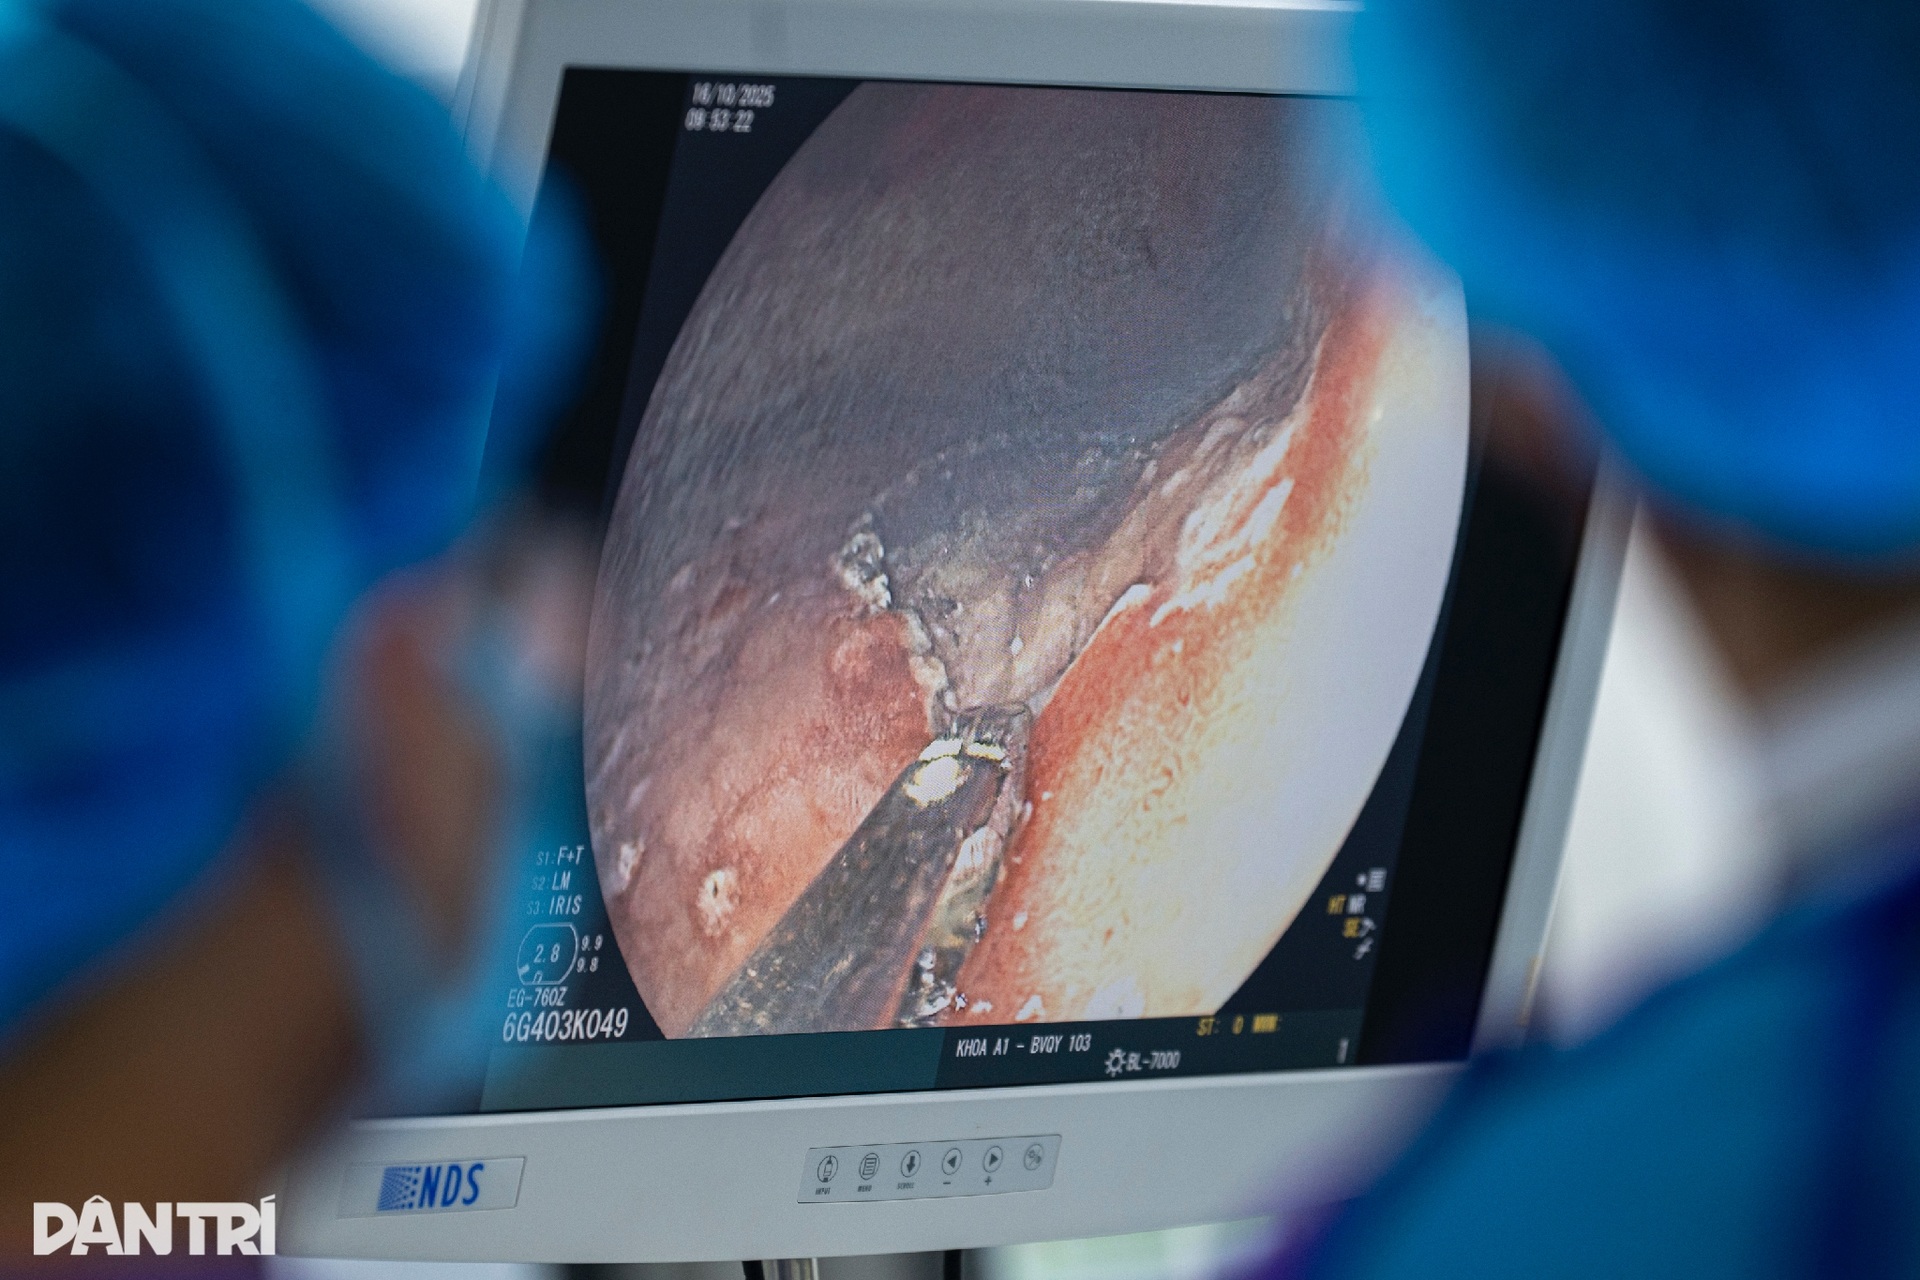

9h05, ê-kíp kỹ thuật đã tiếp cận tới tổn thương. Đây là một khối mô gồ lên, có màu hồng, lõm ở trung tâm.

Dựa vào các xét nghiệm trước đó và hình ảnh đang hiển thị trên màn hình nội soi, BS Phạm Châu trao đổi với ê-kíp trong lúc mổ: “Tổn thương ở vị trí khó - góc bờ cong nhỏ dạ dày, do vậy ca mổ sẽ thêm phần thử thách”.

Sau khi xác định được vị trí, ê-kíp tiến hành tiêm nâng, bóc tách lớp niêm mạc ra khỏi ống tiêu hoá. Bác sĩ Châu sử dụng thiết bị chuyên dụng đánh dấu các vị trí cách ranh giới tổn thương khoảng 2-3mm. Mục đích của việc này là loại bỏ hết hoàn toàn khối mô có nguy cơ ung thư sớm ở dạ dày.

Bước tiếp theo là cắt và bóc lớp niêm mạc tổn thương ống tiêu hoá. Ê-kíp kỹ thuật theo dõi sát sao diễn biến trên màn hình nội soi và các chỉ số của bệnh nhân hiển thị trên máy theo dõi liên tục.